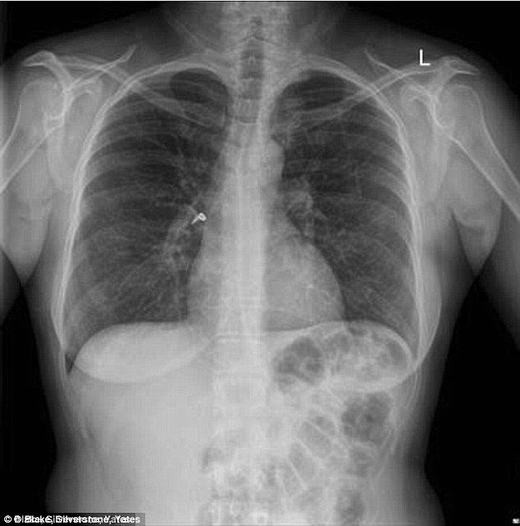

Hít... 1 chiếc khuyên tai vào phổi

Một phụ nữ 41 tuổi người Úc đã phải nhập viện trong tình trạng ho ra máu, khò khè, thậm chí rất khó thở. Tại bệnh viện St Vincent ở Sydney, người ta đã chụp X-Quang và phát hiện trong phổi cô có 1 chiếc khuyên tai.

Có thể thấy rõ chiếc khuyên tai. (Ảnh: Internet)

Chiếc khuyên tai chính là thứ bị mắc kẹt trong ống hít và bị cô đưa vào phổi qua đường mũi. Các bác sĩ đã mổ nội soi để lấy vật thể này ra sau đó.